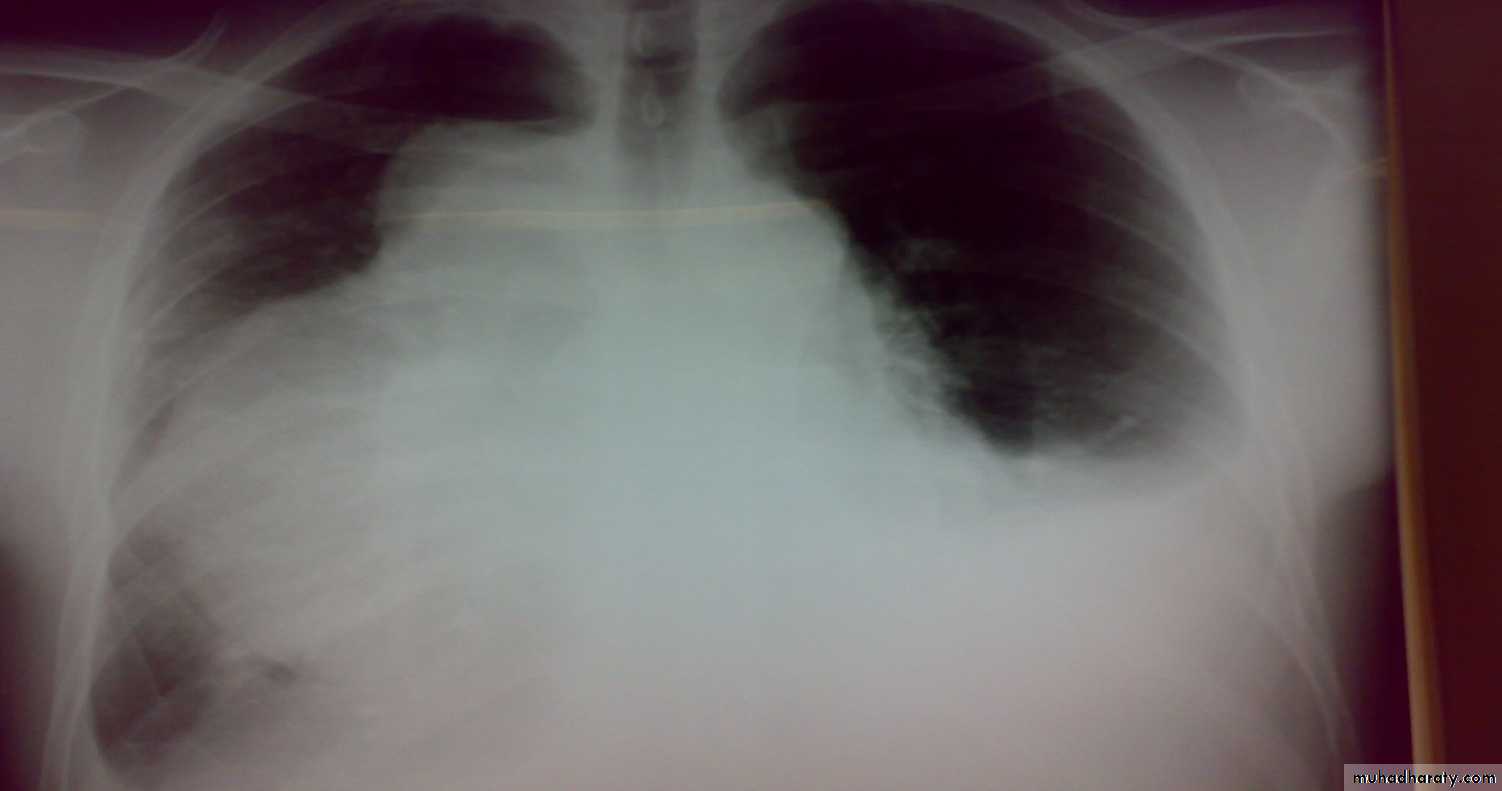

• Bronchiectasis

• Is a persistent abnormal dilatation of the bronchi generally beyond the sub segmental level , generally classified as three types cylindrical , varicose & saccular . The left lower lobe is more commonly involved then the right lower lobe .• Aetiology :-

• It includes (Bronchiectasis , situs inversus ,sinusitis ,sperms hypo motility ) .It represents genetic disorder with abnormal ciliary motility so impaired clearance of sputum with the resultant bronchiectasis .• Clinical manifestation :-The onset is mostly in childhood whereas symptoms generally appear in the second or third decade of life .The disease is more common in females .Major symptom cough with the production of purulent sputum with fetor oris .50% of the patients presented with haemoptysis .Others present with repeated RT infection .,others develop osteo arthropathy & finger clubbing which will resolve with treatment .

• 2-Plain CXR may shows prominent vascular marking .

• 5-Chest CT is the single non invasive tool for both diagnosing &assessing the severity of the disease .